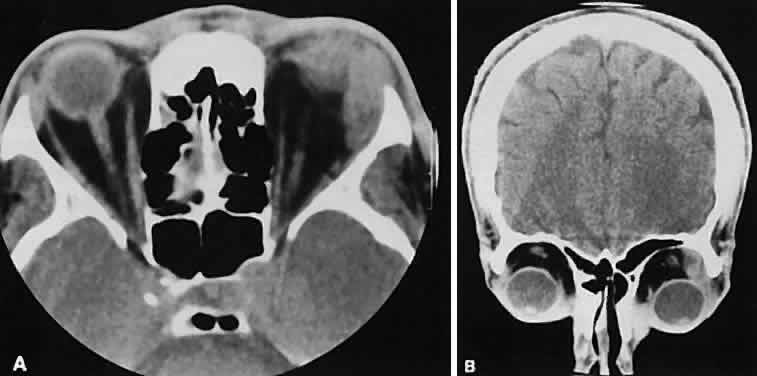

Fig. 7. Graves' orbitopathy with two variations. Axial (A) and coronal (B) views show symmetric fusiform enlargement of the extraocular muscles with tapered muscle insertions. Note the predominant enlargement of the inferior, medial, and superior rectus muscles with lesser involvement of the lateral rectus muscle, a frequent pattern of enlargement in Graves' orbitopathy. Axial (C) and coronal (D) views of Graves' orbitopathy with expansion of retrobulbar ground substance and relative sparing of the extraocular muscles.